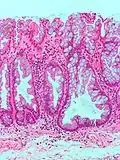

Micrograph of a Peutz–Jeghers colonic polyp – a type of hamartomatous polyp. H&E stain.